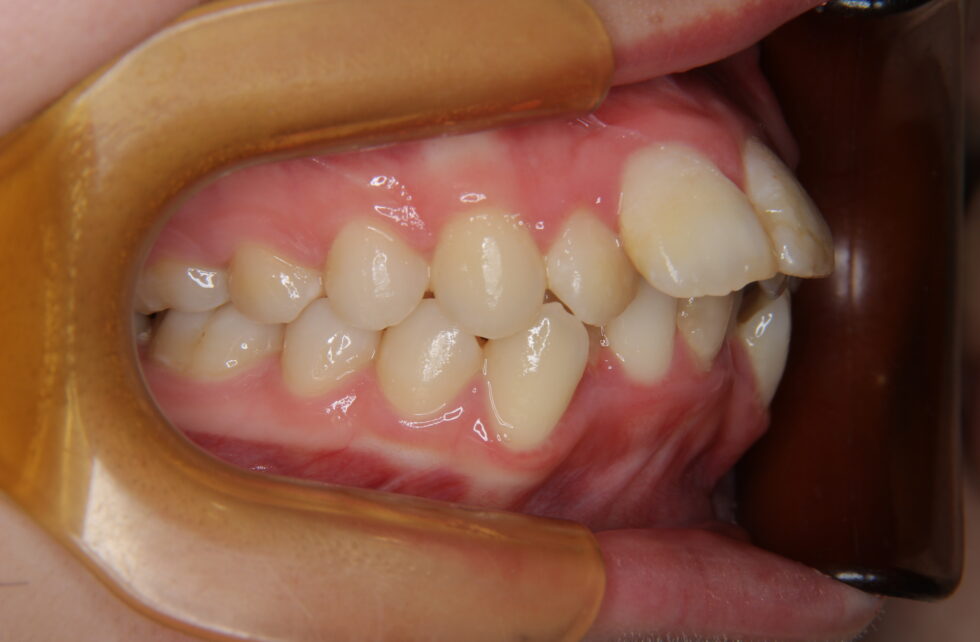

初診時年齢18歳の女性。叢生を伴う上顎前突のケース。

前歯の突出と乱れを気にしておられました。マルチブラケット装置を使用して、上下顎左右側小臼歯の抜歯による動的治療を行いました。突出していた前歯を後退し、乱れも改善することが出来ました。動的治療期間は2年10ヶ月間